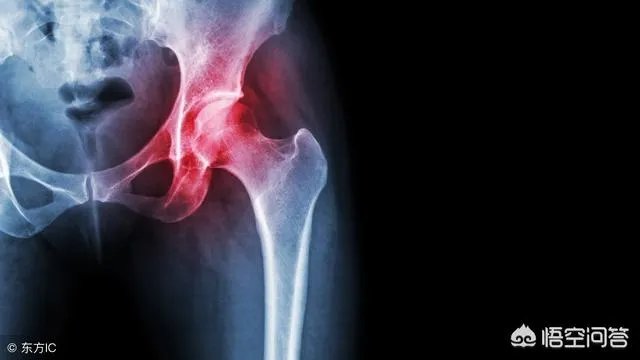

作为一名骨外科医生,临床工作上还真的遇到不少这样的病人,下面就结合个人实际讲讲遇到的运气比较好的病人吧!主任曾经说过,见过一个长期喝酒导致一侧股骨头坏死的患者,20年前就因为疼痛过来看病的,当时主任还是个年轻大夫,因为没有做关节置换的指征,于是就给病人做了保守治疗,并同时跟患者说:如果后期出现疼痛加剧,股骨头坏死加重塌陷的话,可能需要行关节置换手术.......

然而20年过去了,每一次这个病人来复查的时候,股骨头坏死情况真的一次比一次差,病人逐渐出现股骨头坏死塌陷,因为单看片子来说,已经具有手术的适应症了,主任多次劝该患者做手术。

但患者目前至今仍未行关节置换手术,因为他股骨头虽然坏死,但老人家不痛,关节活动也没有明显受限,能走能睡,但他一早就把酒戒了!单看片子来说,是已经有明显的手术指征了,但病人没有明显症状、不影响关节活动,不希望做手术,做完有可能比现在还痛!!

这个幸运的老人家是个特例,但这个病人告诉我们:长期喝酒容易导致股骨头坏死,早期戒酒可以避免股骨头的进一步坏死!对于股骨头坏死的病人,也都不是全部需要做关节置换手术!患者生活质量不明显受限,能多挨一年是一年!写这个病例的目的在于强调对于特殊病人、特殊疾病需要特殊对待,而不是提倡大家有病在家里扛着,对于疾病的诊治,听医生的还是没错的!